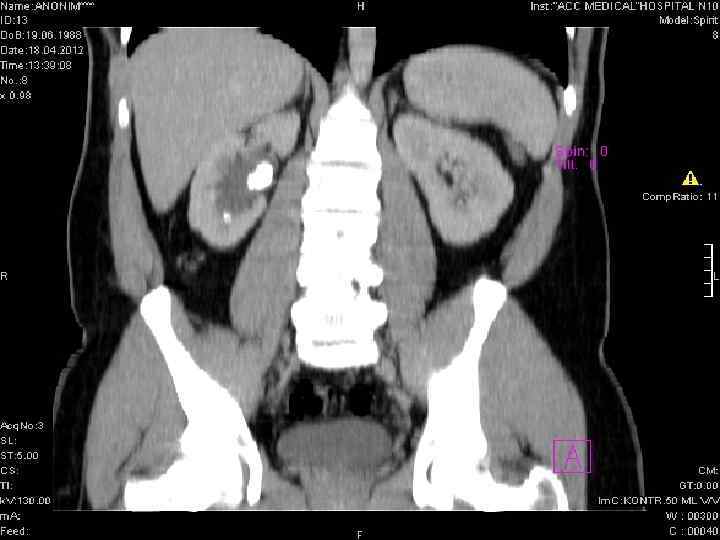

Компьютерлік томография • Несеп тастарын бүйрек кальцификат-тарынан (туберкулезде, эхинококта, ісіктерде), кальцийленген лимфа түйіндерінен, өт тастарынан, ішектегі контраст заттың қалдықтарынан, флеболиттерден, жамбас веналарынан, ішектегі бөгде денелерден жіктеу қажет болатын бірқатар жағдайларда қолданылады.

Бүйректің оң жағындағы тас (оксалат). Бүйректің сол жағындағы тас.